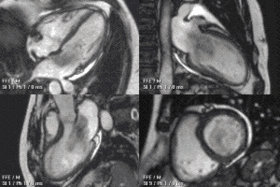

![]() An example of CMR movies in different orientations of a cardiac tumor - in this case, an atrial myxoma.[1] | |

A 4 chamber view of the heart using SSFP cine imaging. Compare the image orientation (4 chamber) with the short axis view of the movie above